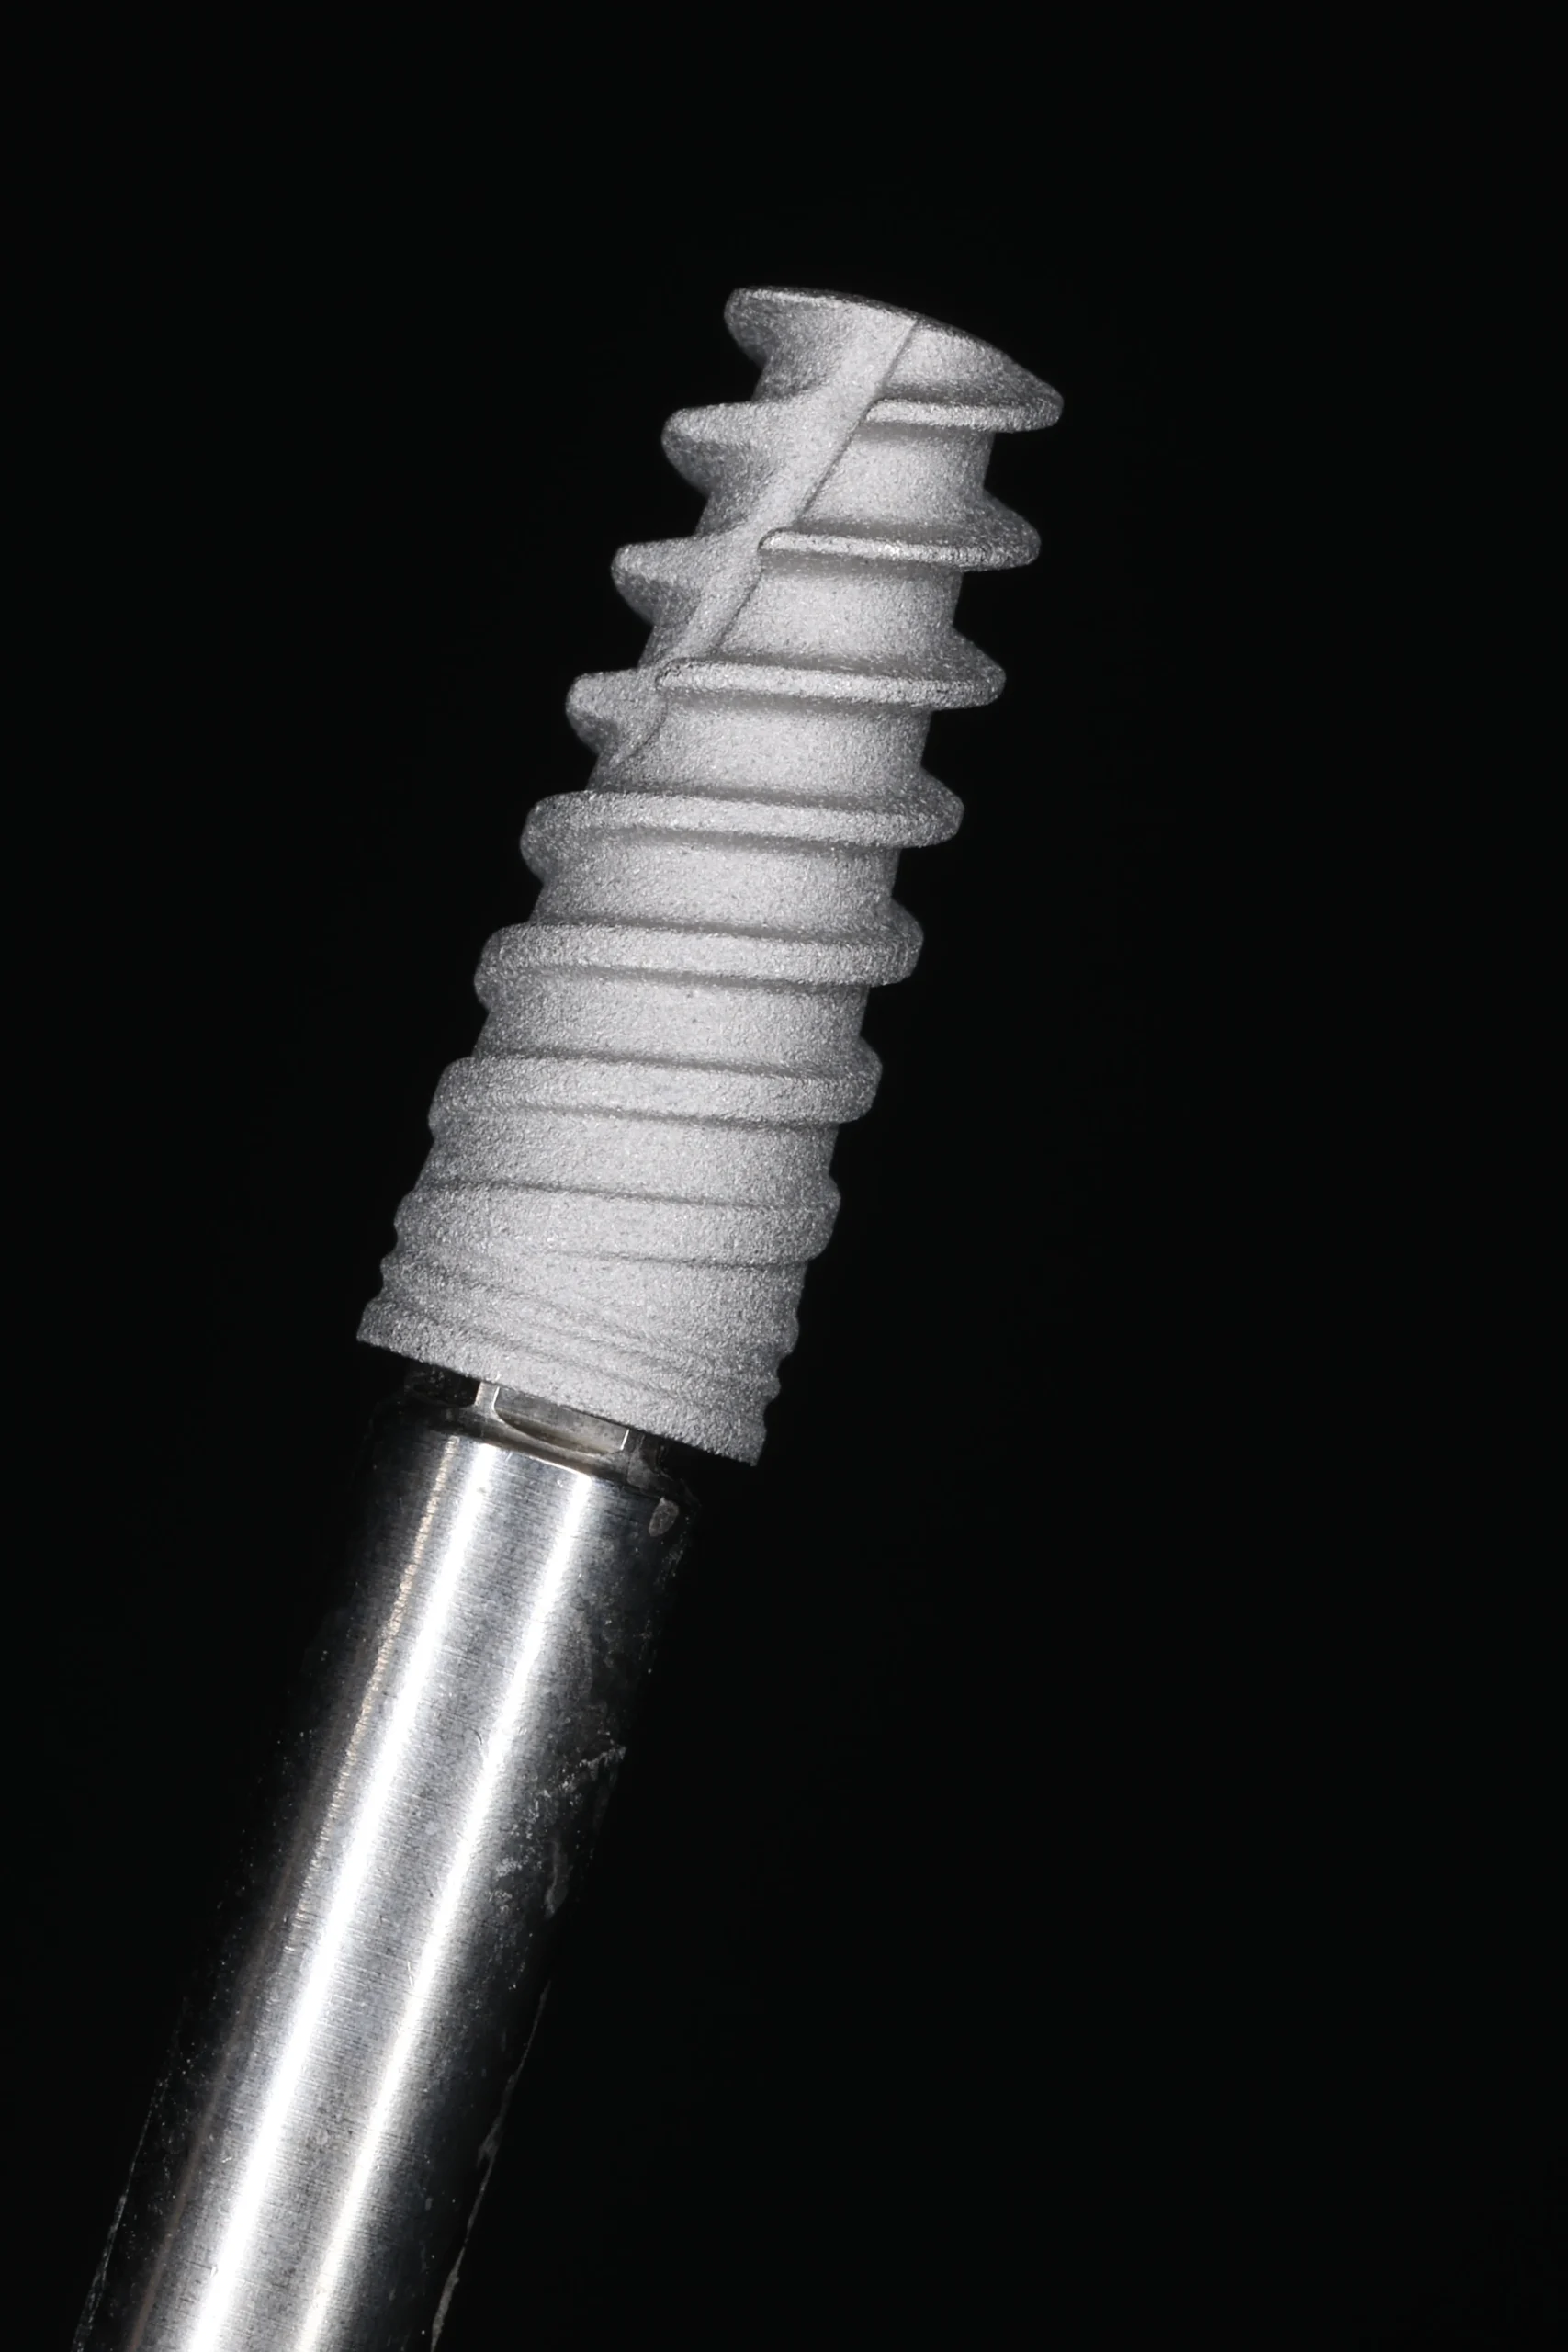

- Implantes endoóseos de titanio.

¿Qué es la implantología?

La implantología es la especialidad que reemplaza dientes perdidos mediante tornillos de titanio (implantes) que actúan como raíces artificiales. Permiten soportar coronas, puentes o sobredentaduras, devolviendo la masticación, el habla y la estética con resultados naturales y previsibles.